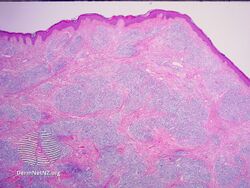

IgG4-related skin disease is the recommended name for skin manifestations in IgG4-related disease (IgG4-RD).[1] Multiple different skin manifestations have been described.

Although a clear understanding of the various skin lesions in IgG4-related disease is a work in progress, skin lesions have been classified into subtypes based on documented cases:[2]